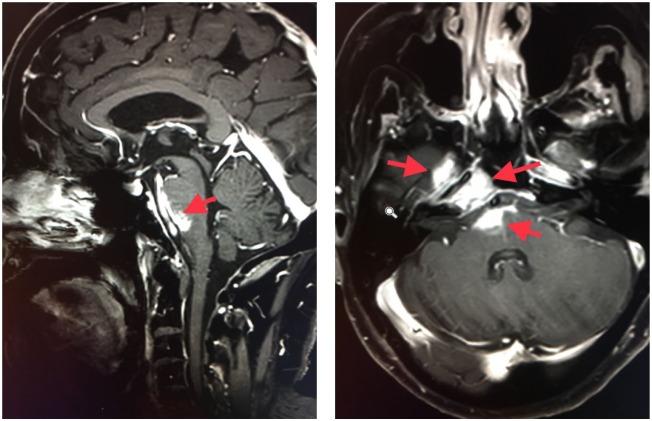

A 72-year-old gentleman presented with facial neurological deficits and a dermal nodule and was diagnosed with spindle cell squamous cell carcinoma with perineural invasion. His course was notable for early intracranial metastasis with progressive neurological deficits despite recurrent radiation therapy with intermittent response. When progressive left-sided weakness prompted imaging evaluation that was concerning for disease recurrence after exhaustion of radiation therapy options, the patient was started on systemic therapy with the anti-PD-1 monoclonal antibody treatment prior to the approval of cemiplimab. Pembrolizumab was chosen due to the fact that the patient was ineligible for clinical trials and for its every 21-day dosing. With this treatment, he has achieved a durable clinical response, resulting in near resolution of neurological deficits and more than a year of progression-free survival to date, despite aggressive intracranial disease.

一名72岁男性患者出现面部神经功能缺损和一个皮肤结节,被诊断为伴有神经周围侵犯的梭形细胞鳞状细胞癌。他的病程特点是早期颅内转移,尽管反复进行放射治疗且有间歇性缓解,但仍出现进行性神经功能缺损。当进行性左侧肢体无力促使进行影像学评估,提示在放射治疗方案用尽后疾病复发时,在西米普利单抗获批之前,该患者开始接受抗PD-1单克隆抗体的全身治疗。选择派姆单抗是因为该患者不符合临床试验条件,且其给药周期为每21天一次。通过这种治疗,他获得了持久的临床缓解,神经功能缺损几乎完全缓解,至今已无进展生存超过一年,尽管颅内疾病进展迅速。